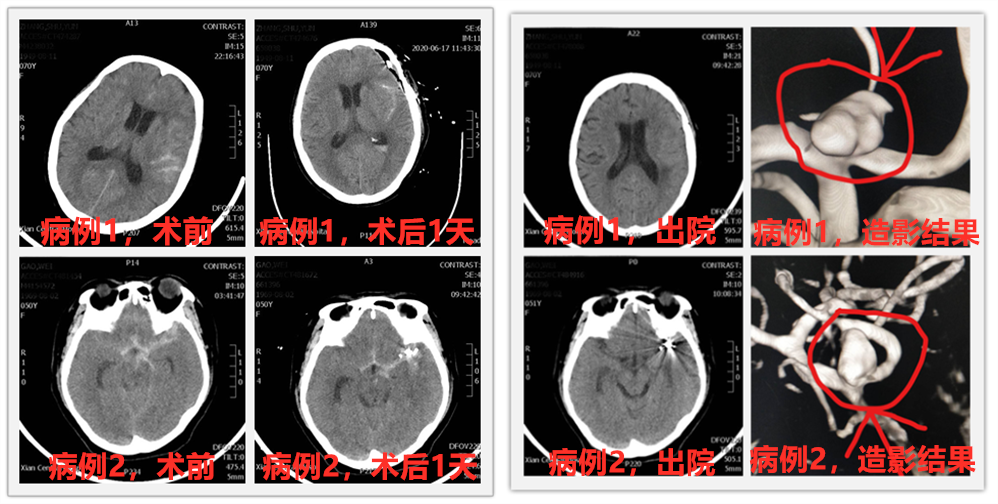

说完这么多理论,这不,色花堂 神经外科最近就有两位蛛网膜下腔急性出血患者,经过脑血管造影诊断,查出分别是颅内不同血管上的动脉瘤,根据病情需要及患者家属要求,科室施展十八般武艺对付这个“坏家伙”,分别为两位患者安排了开颅动脉瘤夹闭术及颅内动脉瘤介入栓塞术,经过积极治疗,患者都康复出院,回归正常生活,获得了患者及家属的一致好评。